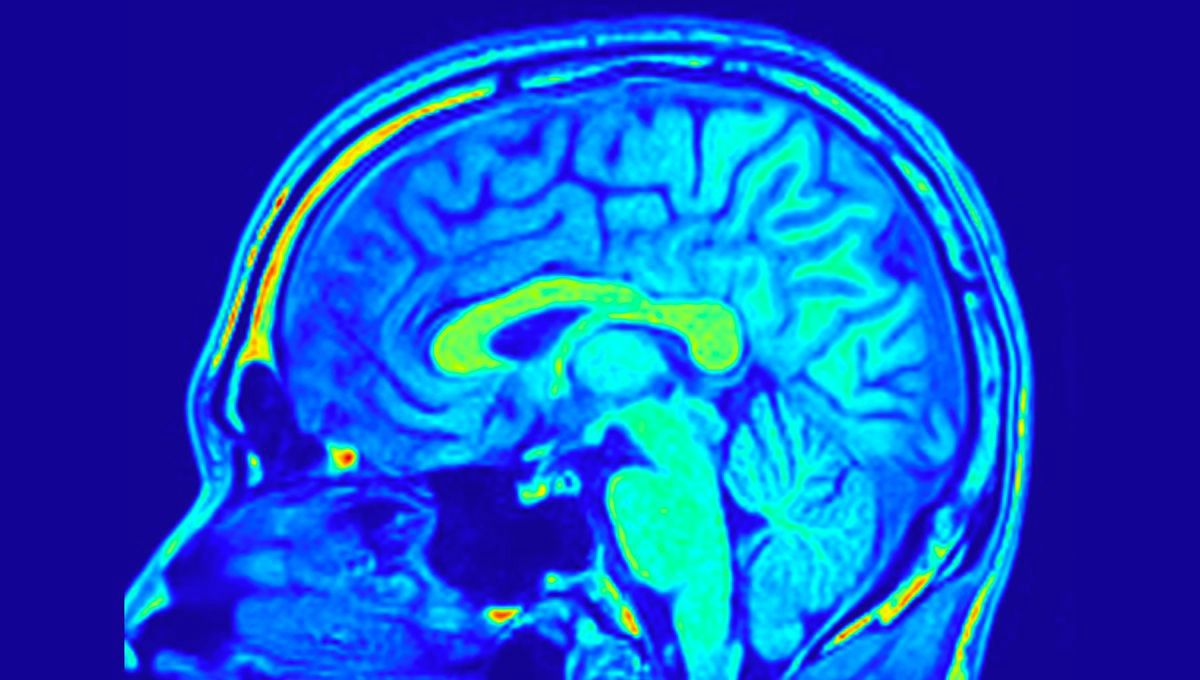

Brain Network That Supports Logic, Reason, And Problem-Solving Pinpointed By New Tests

The results could lead to new ways to identify people with frontal lobe dysfunction in the future.